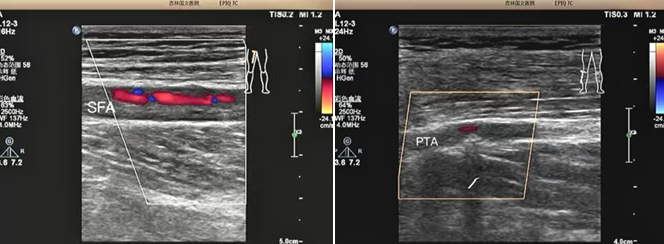

該患者是一位老年男性,因 “雙小腿麻木、發(fā)涼 2 個月” 前來我院就診。超聲科為其進行下肢動靜脈彩超檢查時,精準發(fā)現(xiàn)其股淺動脈及脛后動脈存在重度狹窄至閉塞的情況。超聲檢查憑借其無創(chuàng)、便捷的獨特優(yōu)勢,在第一時間就為臨床治療提供了準確無誤的診斷依據(jù),為后續(xù)治療方案的制定奠定了堅實基礎。

超聲檢查以其無創(chuàng)、便捷、可重復的顯著優(yōu)勢,在此次診療過程中發(fā)揮了重要作用,清晰地顯示了患者下肢動脈的病變情況:1、準確判斷病變部位:精準定位到股淺動脈及脛后動脈。2、明確病變程度:確定為重度狹窄至閉塞。3、評估側(cè)支循環(huán)建立情況:為治療方案的制定提供了關鍵參考。